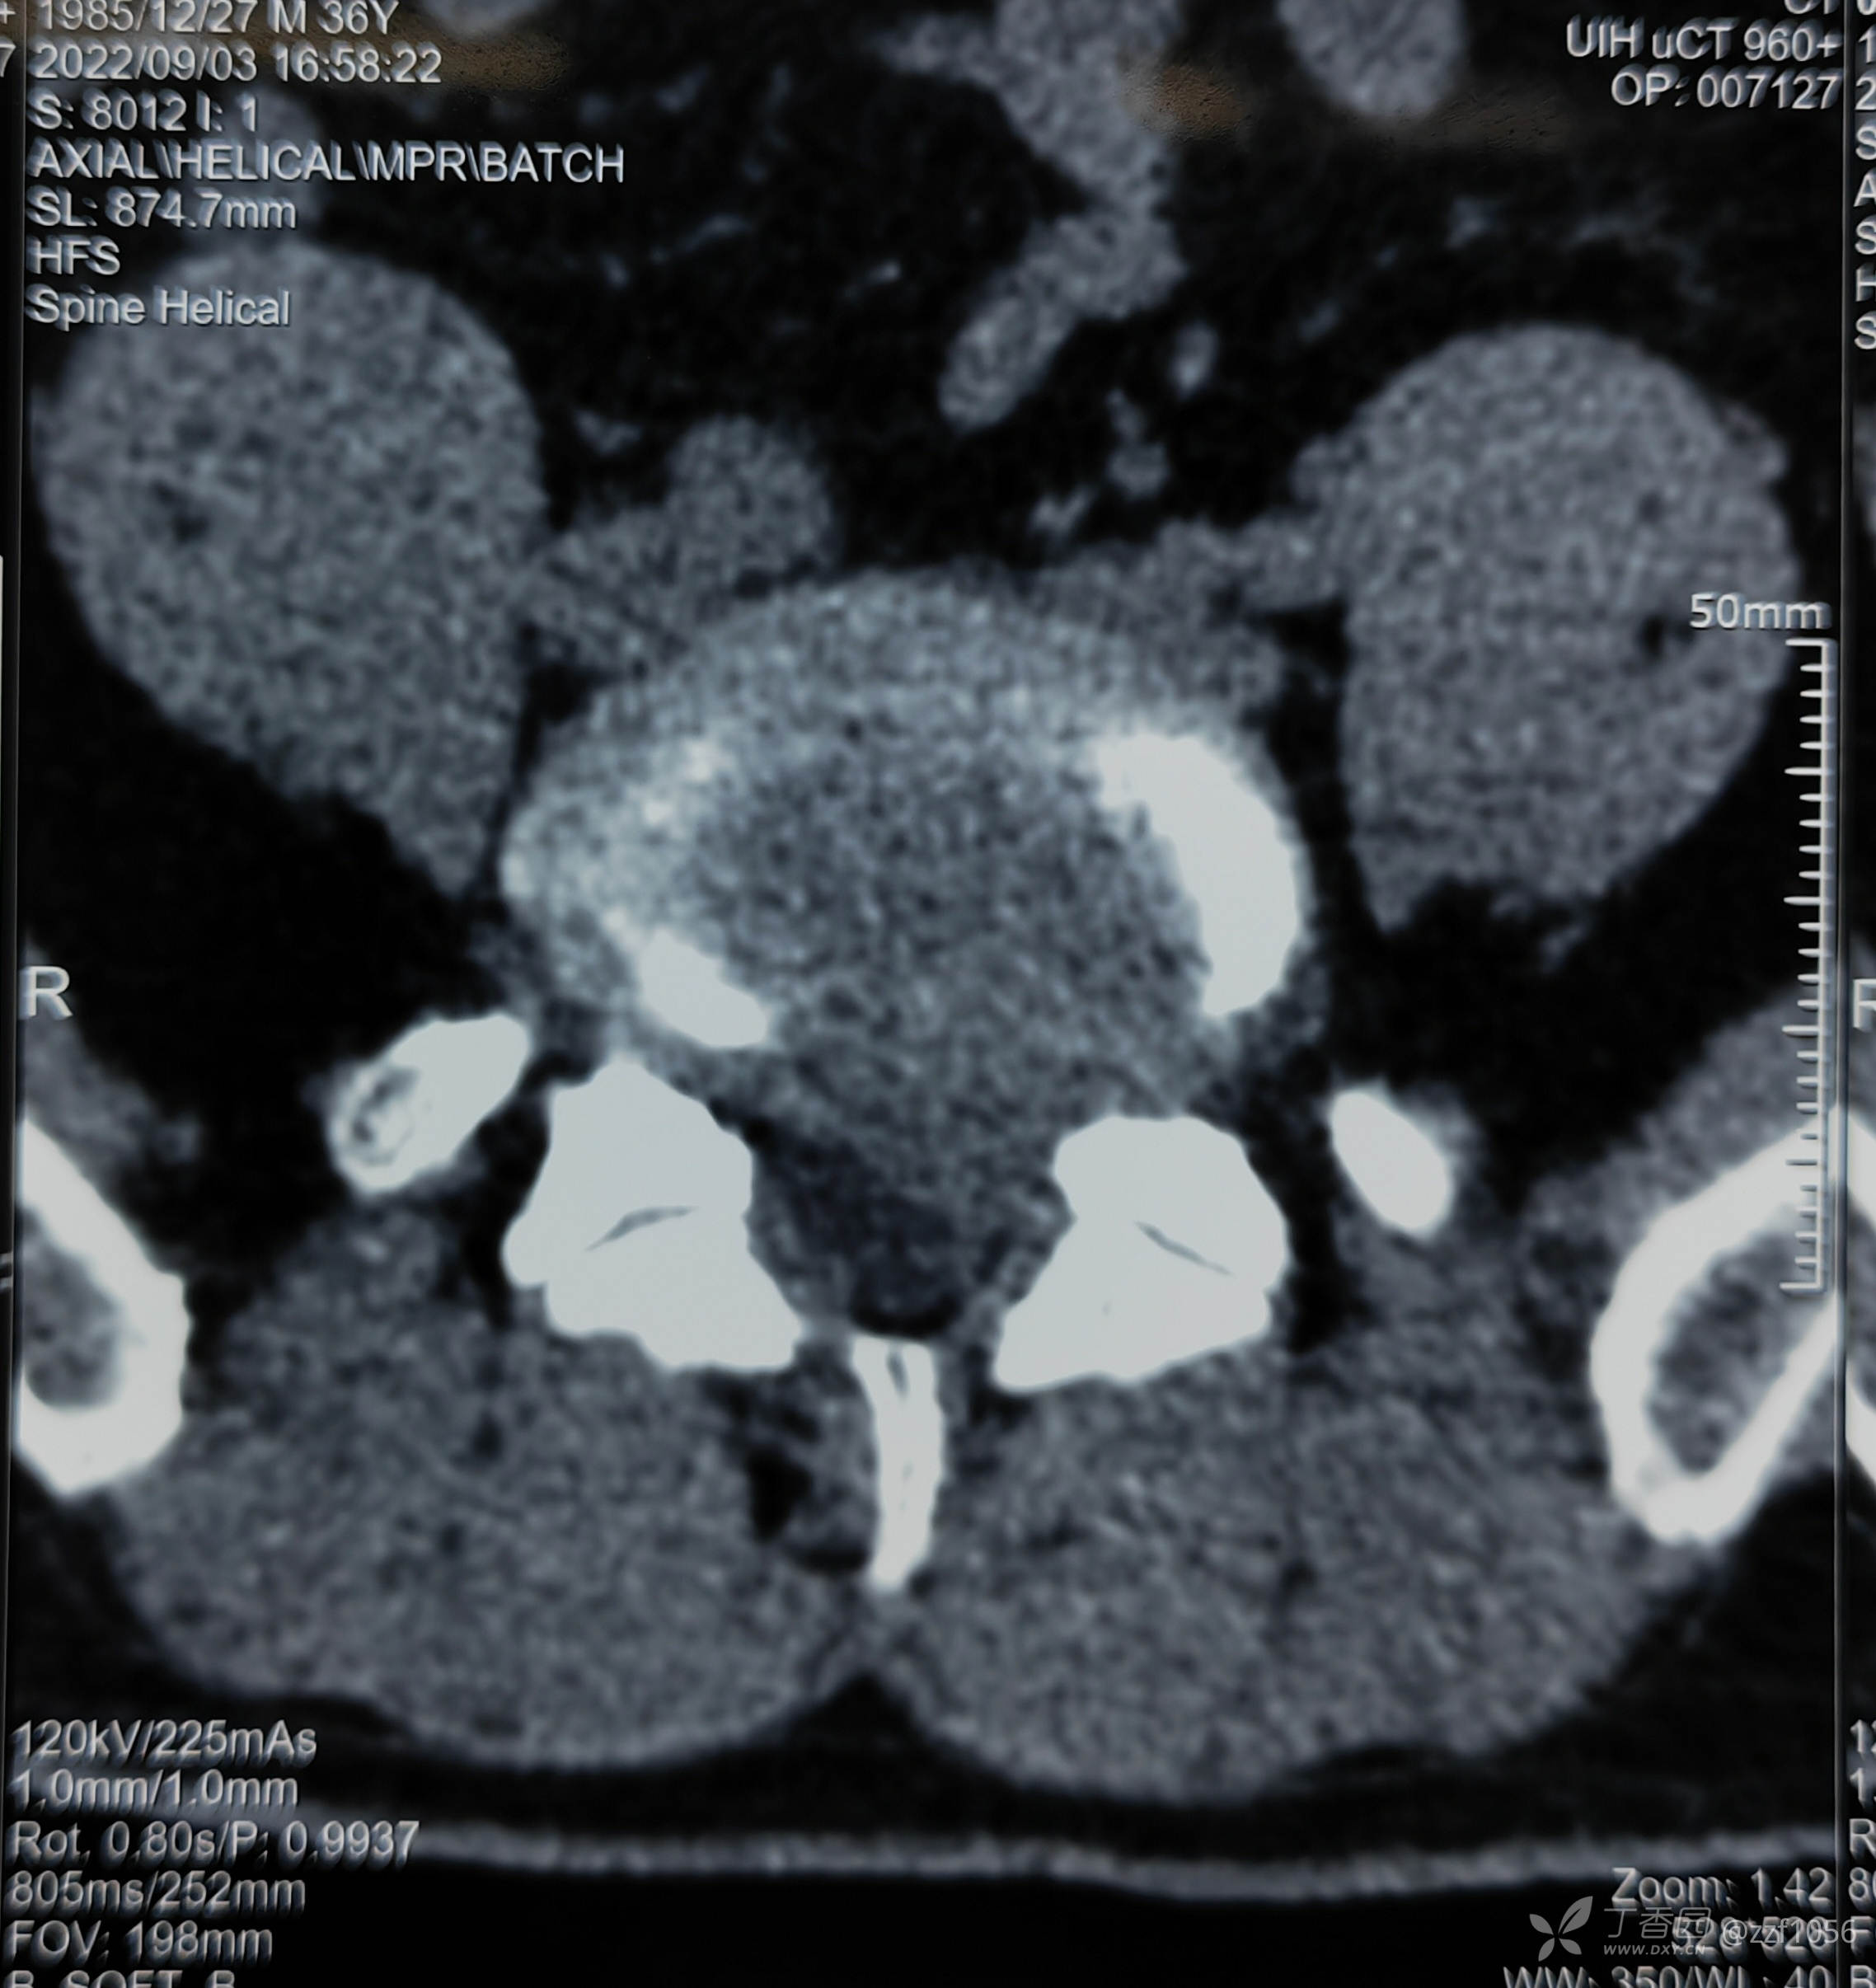

肋骨够数吗?

L1还是T12,三长四短五肥大